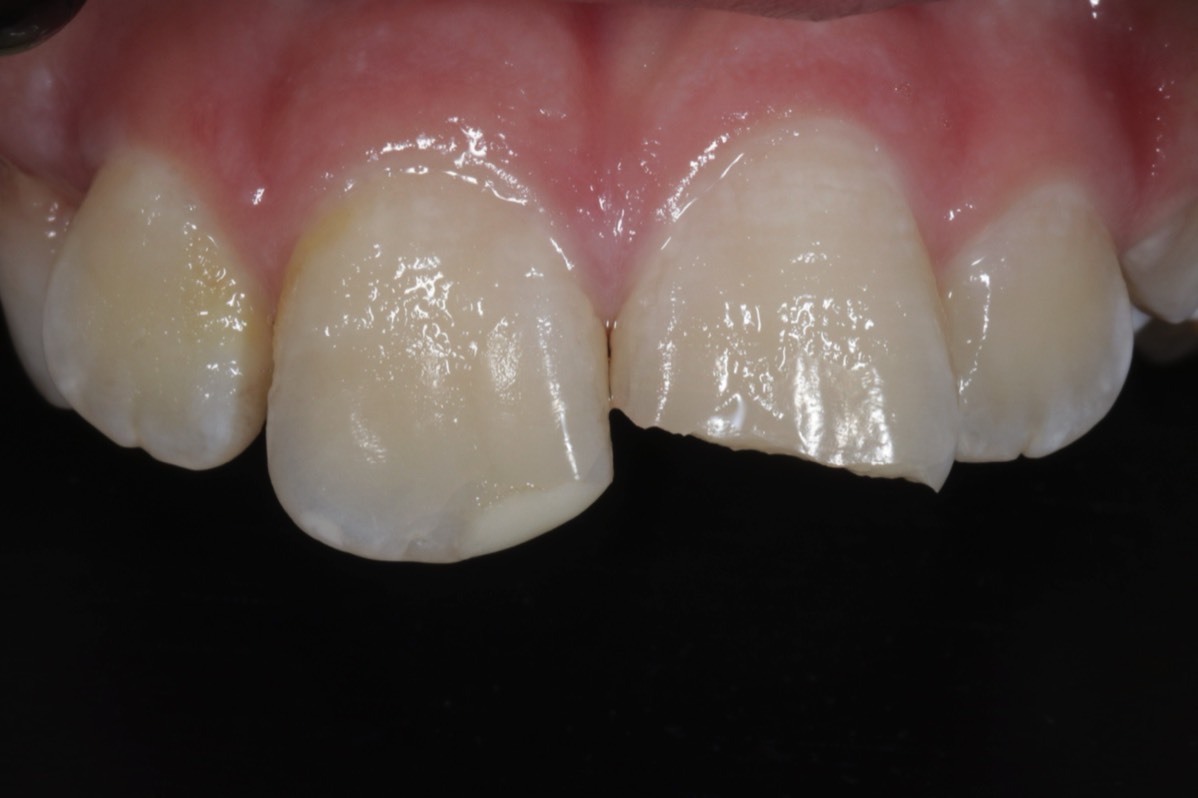

Karies ist eine der häufigsten Zivilisationserkrankungen der Welt. Eine rechtzeitige und minimalinvasiver Behandlung ist das A und O für einen langfristigem Zahnerhalt. Moderne Materialien und ausgefeilte Techniken ermöglichen eine naturgetreue und minimalinvasive Rekonstruktion der kariesgeschädigten Zähne mit einer zahnfarbenen, keramikhaltigen Kompositffüllung.

Nach einem Zahnunfall ist schnelle und Ziel gerichtete Hilfe sehr wichtig, um langfristige Schäden oder Zahnverlust zu vermeiden. So können z.B. abgebrochene, mitgebrachte Zahnfragmente, wieder angeklebt werden. Sogar ganz heraus geschlagene Zähne lassen sich unter Umständen wieder eingesetzen, wenn man diese fachgerecht lagert (Zahnrettungsbox) und schnell genug handelt.